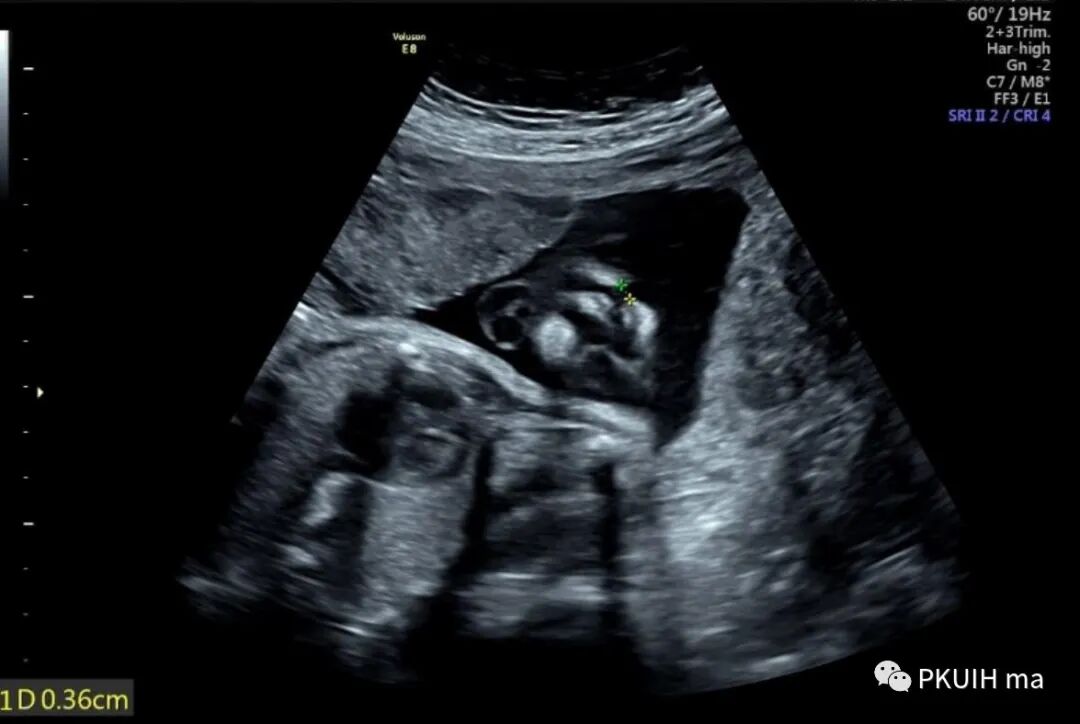

看看下面一例,当时外院诊断Ⅲ度,我个人觉得Ⅱ度(报告没有分度),此例也是男孩,目前快两岁了术后非常好,一点也看不出来异常。